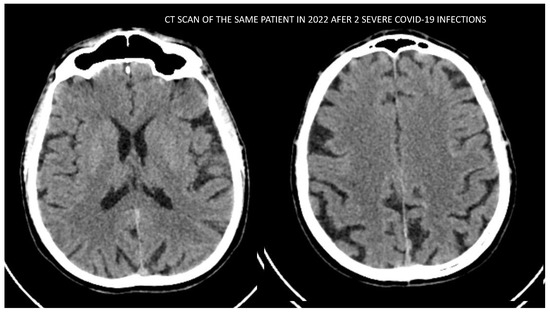

Finally, we present the neuroimaging examinations of one of the patients from the group with evidence of cortical atrophy. His imaging findings are the most distinguishing and demonstrative and show explicitly the damaging effect due to severe COVID-19 infection on the brain structures. The patient had no history of any previous infection cognitive complaints; he did not suffer from any neurodegenerative disease nor had any history of hypertonia, obesity or any family history of dementia or psychiatric disorders. According to the anamnestic data from his family, he led a healthy lifestyle, had a BMI in the normal range, was nonsmoker and had no history of alcohol abuse/addiction. At the time of our investigation, he was 58 years old. He had a history of having the COVID-19 infection (in 2021 and 2022) twice with two hospitalizations and pulmonary complications, need for oxygen therapy (up to 10 L/min) and high doses of corticoids (up to 8 mg Dexamethasone per day). The first image (Figure 6) was made in 2020 before the COVID-19 infection. The second image (Figure 7) was made after the acute phase of the second COVID-19 infection. We see significant progression in the severity of the cortical atrophy. In addition to the cognitive decline, this patient presented with organic delusional disorder—mostly expressed by delusions on paranoid themes and later the psychiatric clinical picture changed to nihilistic delusions, which are more typical for depression with psychotic features. Through this period, the general functioning of the patient was dramatically impaired.

Figure 7. CT scan image of the patient conducted in 2022 after surviving 2 severe COVID-19 infections.